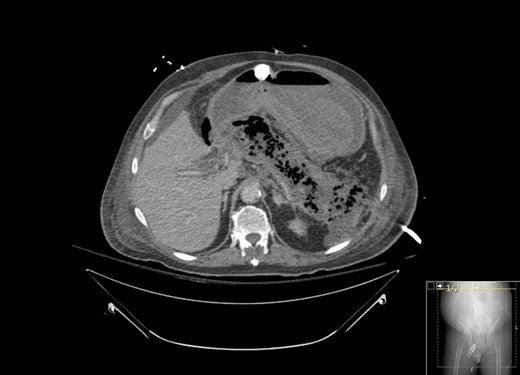

A 67-year-old male presented to his local hospital with postprandial right upper quadrant (RUQ) abdominal pain and vomiting. CT scan of the abdomen and pelvis with oral contrast showed extensive stranding and ill-defined fluid attenuation surrounding his pancreas (Fig. 1). Initial serum amylase and serum lipase levels were 2918 and 17 360, respectively. He was diagnosed with acute, necrotizing, gallstone pancreatitis and developed gastric outlet obstruction (GOO) 9 days after the onset of his symptoms, at which time he was transferred to our institution for further care. On arrival, he had GOO and renal failure (creatinine 2.1 mg/dl). A gastro-jejunal (GJ) feeding tube was placed for jejunal feeds and gastric decompression. On hospital Day 7, the patient’s pain had resolved and a cholecystectomy was attempted laparoscopically, but was converted to open due to inflammation around the infundibulocystic junction. Subsequently, a follow-up contrasted CT showed marked interval necrosis of pancreatic tissue resulting in numerous lobulated soft tissue and gas collections in the upper abdomen, midline upper pelvis, and in the gallbladder fossa (Fig. 2). A pancreatic drain was placed by interventional radiology (IR) on hospital Day 20 for interval increase in pancreatic necrosis on CT. On hospital Day 23, IR embolization of gastroduodenal artery (GDA) was performed due to GI bleeding. Laparoscopic necrosectomy with malencot drain placement was performed on hospital Day 36. Post-operatively, he had a large upper GI bleed requiring emergent endotracheal intubation and initiation of the massive transfusion protocol. Angiography was performed and was negative. On the following day, hospital Day 39, GI performed an EGD and found hemorrhagic gastritis, but no localizable bleeding. He was placed on high dose PPI, carafate and octreotide. He progressed to acute renal failure with initiation of hemodialysis on hospital Day 45. On hospital Day 47, a follow-up EGD was done with exchange of the gastrojejunostomy tube, and hemorrhagic gastritis was still present. He was transferred to the general surgery inpatient unit the following day. On hospital Day 54, he developed another upper GI bleed requiring ICU transfer. EGD was again performed and the hemorrhagic gastritis remained, but no active site of bleeding was identified. On hospital Day 56, a second look EGD was done with similar findings of hemorrhagic gastritis with no identifiable active bleeding. On hospital Day 58, the patient elected to receive palliative care rather than undergo subtotal gastrectomy. He died 9 days later at home.

CT with contrast showing marked interval necrosis of pancreatic tissue.